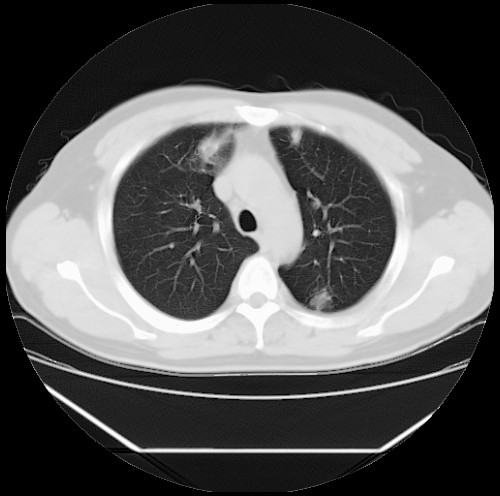

标题: CT22085:双肺多发结节

男,44岁,咳嗽,痰中带血2天。

病灶大部分位于胸膜下,结节大小相差不是很大,肺尖太干净。这种结核没见过,我认为可排除。

首先考虑转移,不除外肉芽肿、真菌感染。建议查其它。

除肺内及胸膜下可见多发大结节外,在肺小叶中心核、小叶间隔及支气管血管束上亦可见多方小结节,可以认为是随机分布。考虑转移可能性大。

仔细观察病灶形态,病灶边界部分清楚,结合临床症状,首先考虑转移,纵隔内多个肿大淋巴结影。

双肺血管纹理末端多发类圆形结节,边界光滑清晰 气管前腔静脉后淋巴结肿大

考虑转移瘤

本例双肺多发类圆形高密度灶,边清,结合病史多考虑双肺多发转移改变,可以结合实验室检查。